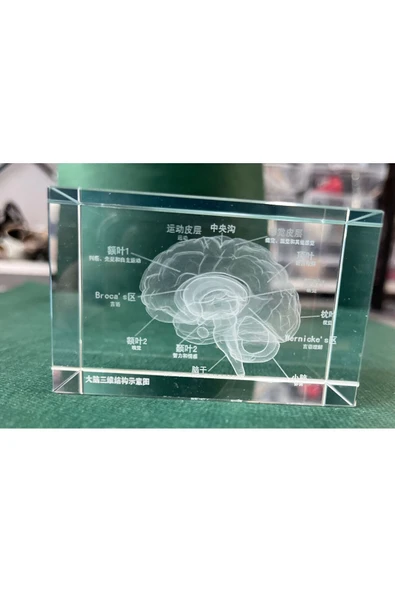

DMA GROUP 3 D BEYİN DETAYLI CAMKÜP İÇİNDE -İŞ-BÜRO-OFİS İÇİNİ KİŞİYE ÖZEL HEDİYELER-FARKLI-BENZERSİZ-YENİ

995.00 TL